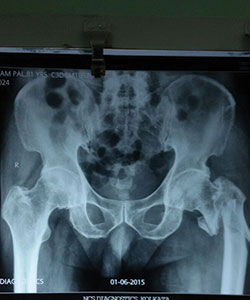

Case 3: Comminuted hip fracture

Comminuted left hip fracture in a 81 years old male patient

X-RAY 1

pre operative x-ray showing comminuted left hip fracture